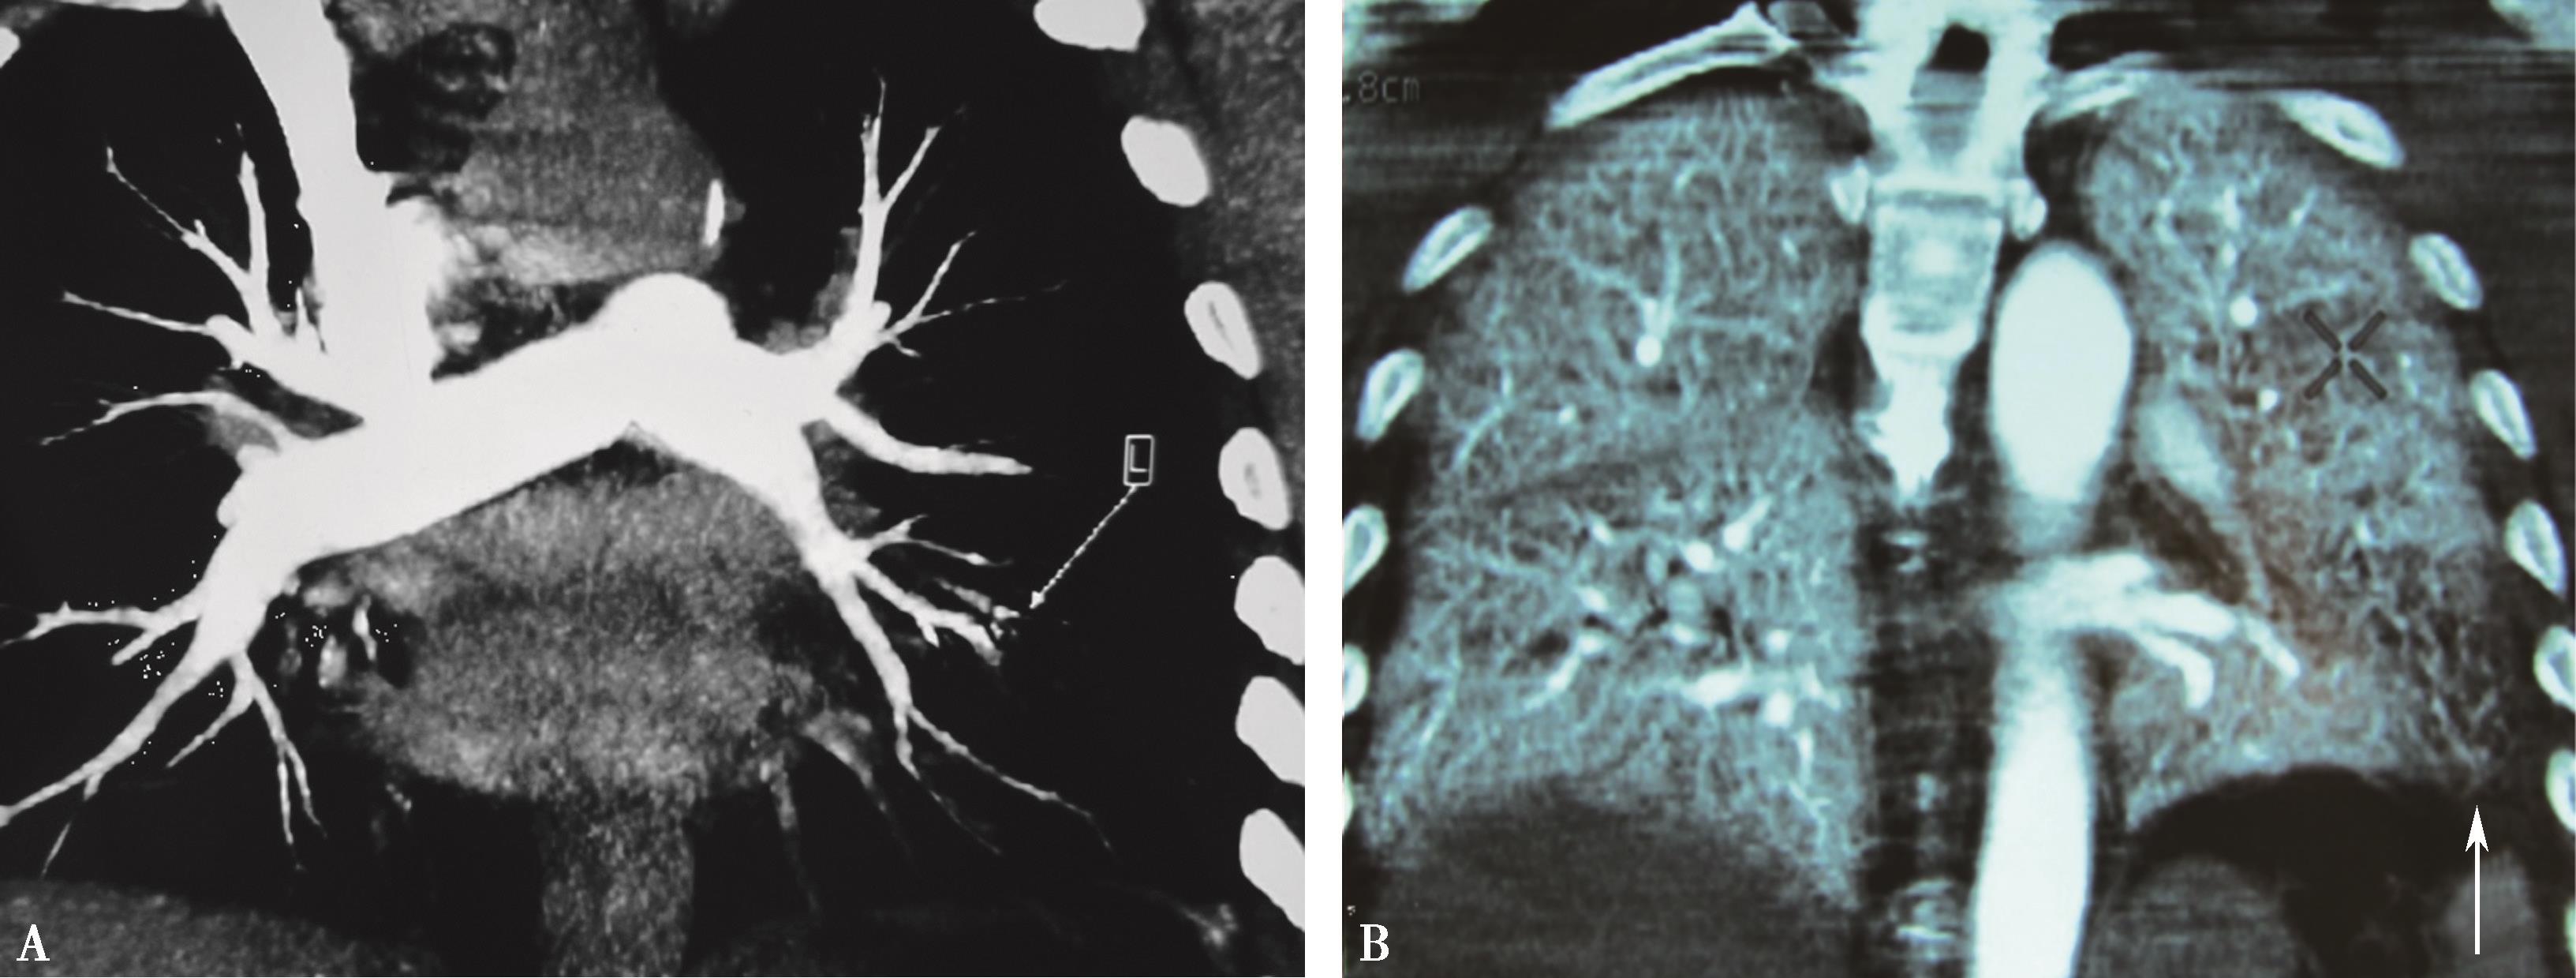

(二)双期扫描法(图8-1-5)

图8-1-5 CTPA两期扫描应用:患者,男,37岁,二尖瓣狭窄,肺循环高压,怀疑肺栓塞。第一期右肺下叶基底段对比剂充盈不充分(ABC↑);第二期充盈充分(DEF↑),排除肺栓塞诊断